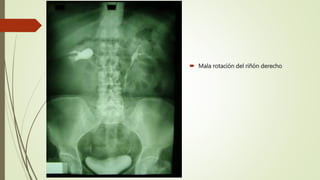

 Mala rotación del riñón derecho

 Mala rotacióndel riñón derecho